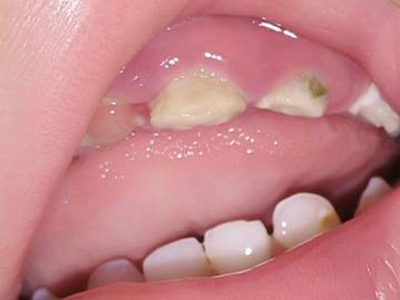

牙齿

白斑

牙釉质发育不全牙齿白斑图

牙釉质发育不全患者可以仅仅出现牙齿色泽和透明度的改变,形成白垩色釉质,即类似于牙齿上有白斑,此时牙冠形态通常较完整。